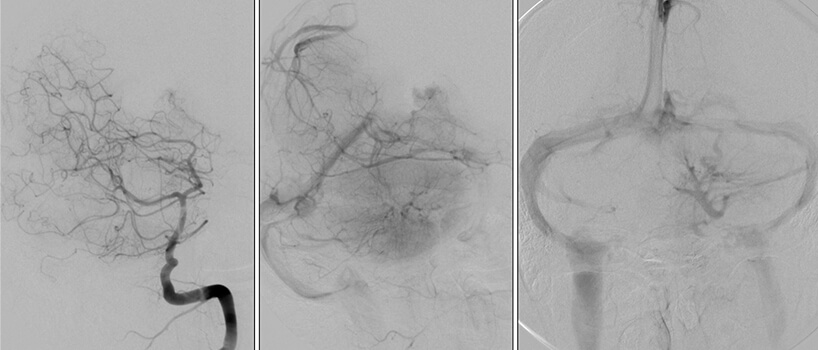

Είναι καλοήθεις δυσπλασίες στο φλεβικό σκέλος, με σηραγγώδεις φλεβικές λιμνάσεις, χωρίς αρτηριοφλεβώδη επικοινωνία. Μπορεί να είναι μονήρεις (σποραδική μορφή) ή πολλαπλές. Στην τελευταία περίπτωση είναι συνήθως οικογενείς και κληρονομούνται κατά τον αυτοσωματικό επικρατούντα χαρακτήρα (χρωμόσωματα 7q21-22(CCM1), 7p13-15(CCM2) και 3q25-27(CCM3)).

Αυξάνονται σε μέγεθος μετά από επεισόδια αιμορραγίας λόγω υποτροπιαζόντων, συρρρεόντων μικροαιματωμάτων που συμβαίνουν σε διαφορετικές χρονικές περιόδους. Εντός της βλάβης διακρίνονται αιμορραγικά στοιχεία σε διαφορετικά χρονικά στάδια (παλαιότερα και πιό πρόσφατα).